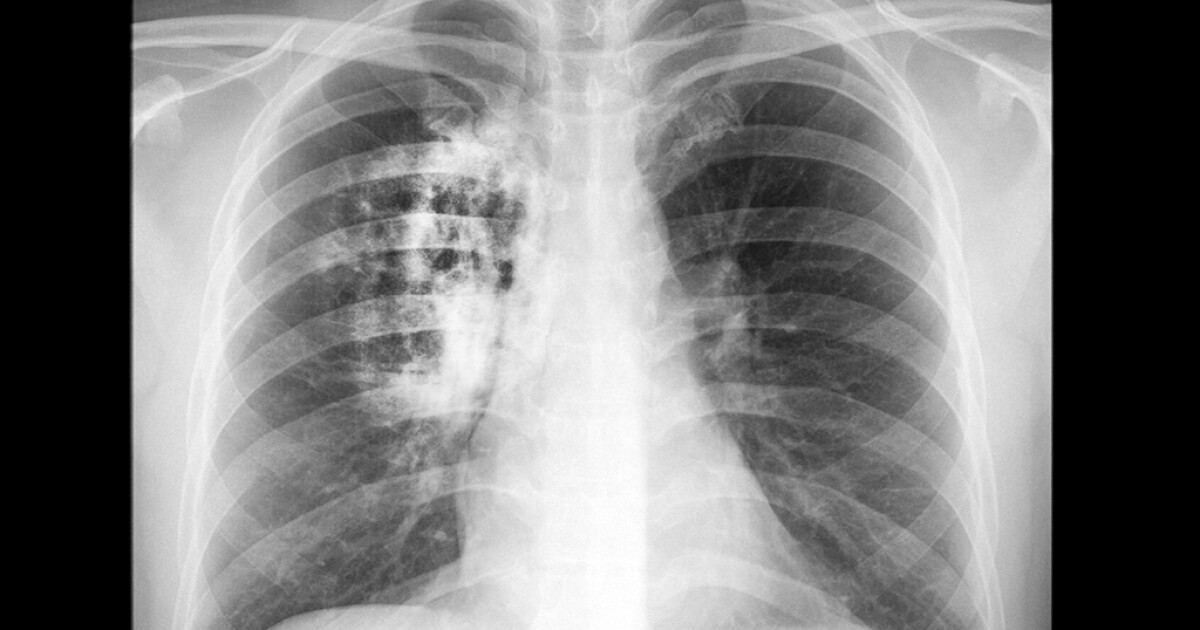

Is There A Blood Test For Lung Cancer . Learn about the imaging tests, biopsies, and lab tests used to diagnose and stage lung cancer. Learn about the signs, risk factors, and tests for lung cancer, and how to get an accurate diagnosis. Lung cancer diagnosis often starts with an imaging test to look at the lungs. The most accurate test is a biopsy, but it may have false positives or. The test may pave the way for a sensitive. If you have symptoms that worry you, a healthcare. Some blood tests used to diagnose cancer include: A complete blood count (cbc) measures the. A test to count your blood cells. A new study shows that a blood test based on metabolomics can identify lung cancer in asymptomatic patients with high accuracy. Find out about the current screening.

Lung Cancer Diagnosis, Tests, and Scans Is There A Blood Test For Lung Cancer Lung cancer diagnosis often starts with an imaging test to look at the lungs. Some blood tests used to diagnose cancer include: A complete blood count (cbc) measures the. Learn about the imaging tests, biopsies, and lab tests used to diagnose and stage lung cancer. The test may pave the way for a sensitive. Learn about the signs, risk factors,. Is There A Blood Test For Lung Cancer.